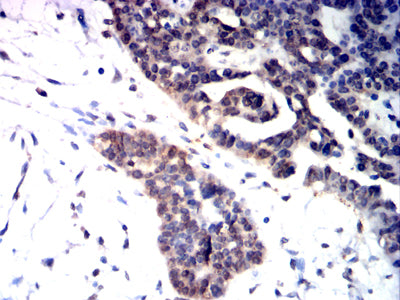

Immunohistochemical analysis of paraffin-embedded human colon cancer tissues using KMT2A mouse mAb with DAB staining.